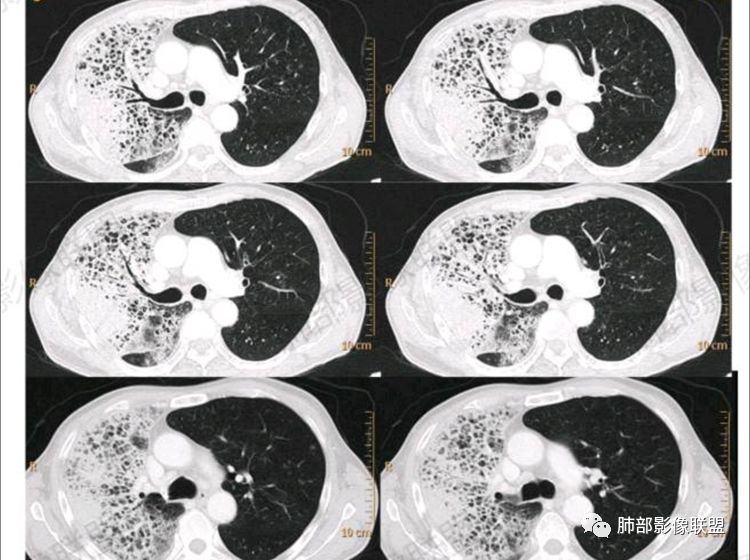

CT:右肺弥漫实变影及磨玻璃影,内见小网格影及蜂窝影,病灶由胸膜下向外进展,明显均匀强化。

右肺叶见混杂阴影,见弥散小网格征,部分融合大网格影,部分见网格小结节征,右肺叶范围广,以右肺上叶及下叶为甚,相应边缘略膨隆,及胸膜下斑块实变强化明显病灶(支气管血管束结构消失),强化密度不均匀,见多发小斑点低密度影,轮廓不清,支气管进入病灶呈“枯树枝”状,远段阻断,左肺舌叶及下叶见多发散在GGO密影,沿支气管血束分布,以肺腺泡分布。纵隔窗实性成份减少,肺肿瘤标志物高,首选粘液性肺腺Ca,无需鉴别!

2.影像显示右肺较广泛蜂窝样阴影,上肺及下肺为主,未见液平及重力分布趋势。其中上叶后段及下叶后基底段近胸膜下可见实性密度区,实性密度区强化明显,周边特征掩盖不清。

2.单肺或单肺叶蜂窝样阴影,CYFRA211增高等应当高度警惕恶性肿瘤,尤其是出现异常强化的实性密度区。正如有老师分析肺腺癌可能性较大!

3.尽管患者咳大量白色泡沫痰,但病灶区未显示重力分布趋势,大范围病灶并未见播散结节,粘液腺癌的可能性降低。病灶浸润破坏能力不强(蜂窝样结构尚存,胸膜受侵较迟等),强化较显著等,肺鳞癌可能性较小。